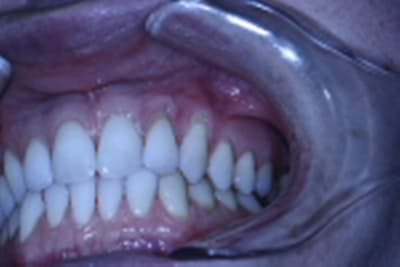

La patiente est jeune, non fumeuse, aucun problème de santé et très préoccupée par son problème de gencive.

Les récessions sont des Cl I de Miller, donc bon pronostic.

Je penchais pour un conjonctif sur 23 et un lambeau semi-lunaire positionné coronairement sur la 22.

Mais dans une même séance ça paraît difficile.